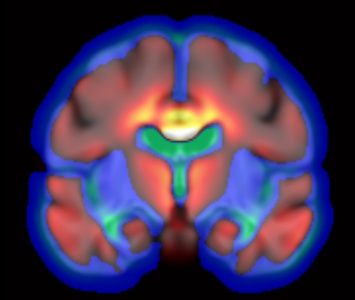

Electrical Geodesics crée, développe et commercialise des procédés et des dispositifs de mesure, d’analyse et d’intervention sur l’activité cérébrale. (suite…)